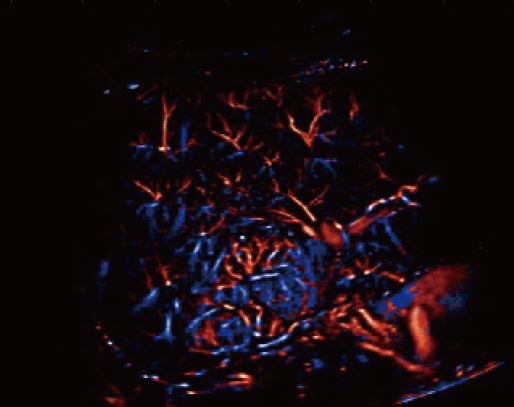

Dotato di un'ampia gamma di tecnologie di imaging innovative, Resona A20 supporta i medici nella ricerca clinica all'avanguardia. La Super Resolution CEUS (SR CEUS) rivela i dettagli della perfusione sanguigna a livello di micron, aiutando i medici nell'esplorazione delle prime alterazioni microcircolatorie nelle lesioni. Inoltre, la visco-elastografia STVi, una tecnica innovativa per la valutazione della viscosit├Ā dei tessuti, dimostra un grande potenziale per gli studi sulle malattie croniche del fegato e sui tumori.

Grazie alla piattaforma AIT, Resona A20 offre una soluzione integrata completa per l'imaging a super-risoluzione, una capacit├Ā finora difficile da raggiungere. La SR CEUS rivela i dettagli intricati del microcircolo delle lesioni a livello di micron, favorendo gli studi di perfusione microcircolatoria in oncologia.

Risoluzione a livello di micron

Capacit├Ā di rilevamento microvascolare

Iperplasia nodulare focale | Mappa densit├Ā

Iperplasia nodulare focale | Mappa direzione

Iperplasia nodulare focale | Mappa velocit├Ā